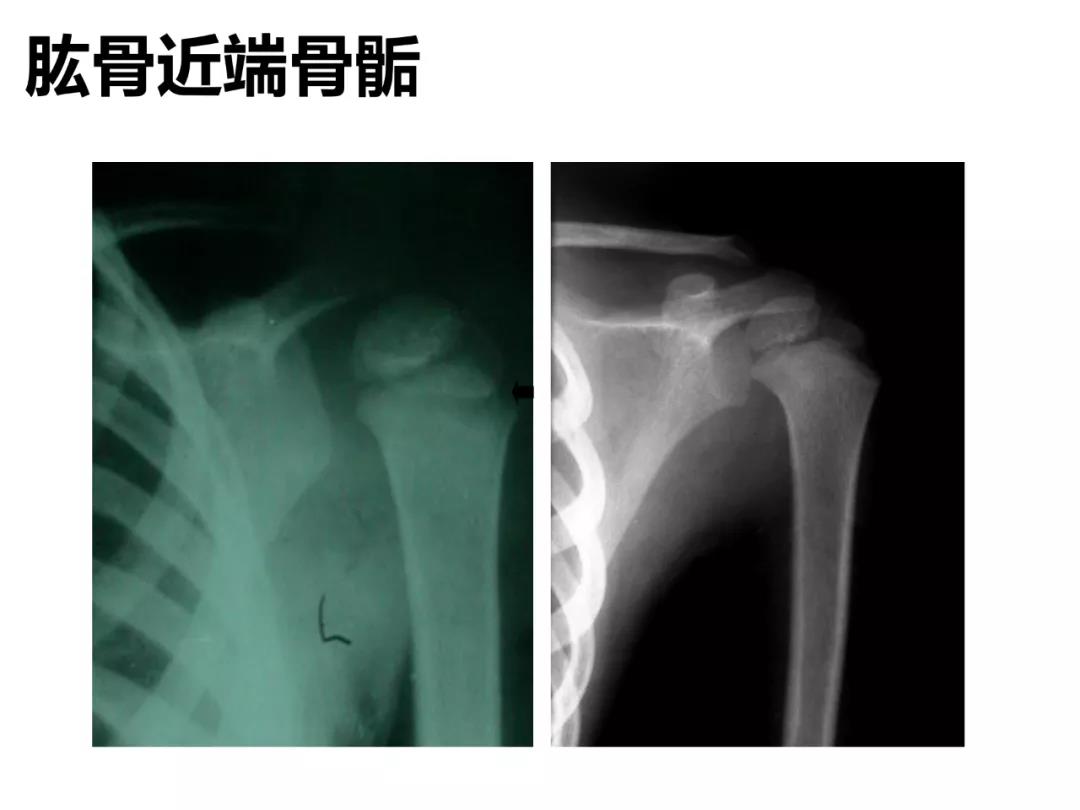

小儿骨科X线片汇总,临床读片宝典!